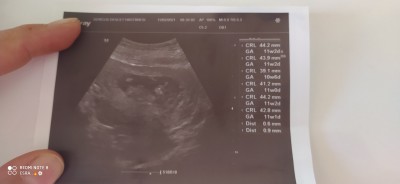

2 Mart 2021 (62 puan) cevapladı

Bunu attım bu olur mu

image

2 Mart 2021 (108 puan) yorumladı

6 yada 7 haftalik olmasi lazim canim

imagebakarmisin 7haftalik bu foto

3 Mart 2021 (251 puan) cevapladı

dila56 buraya attım bakar mısın?

3 Mart 2021 (108 puan) yorumladı

Kiza benziyor canim